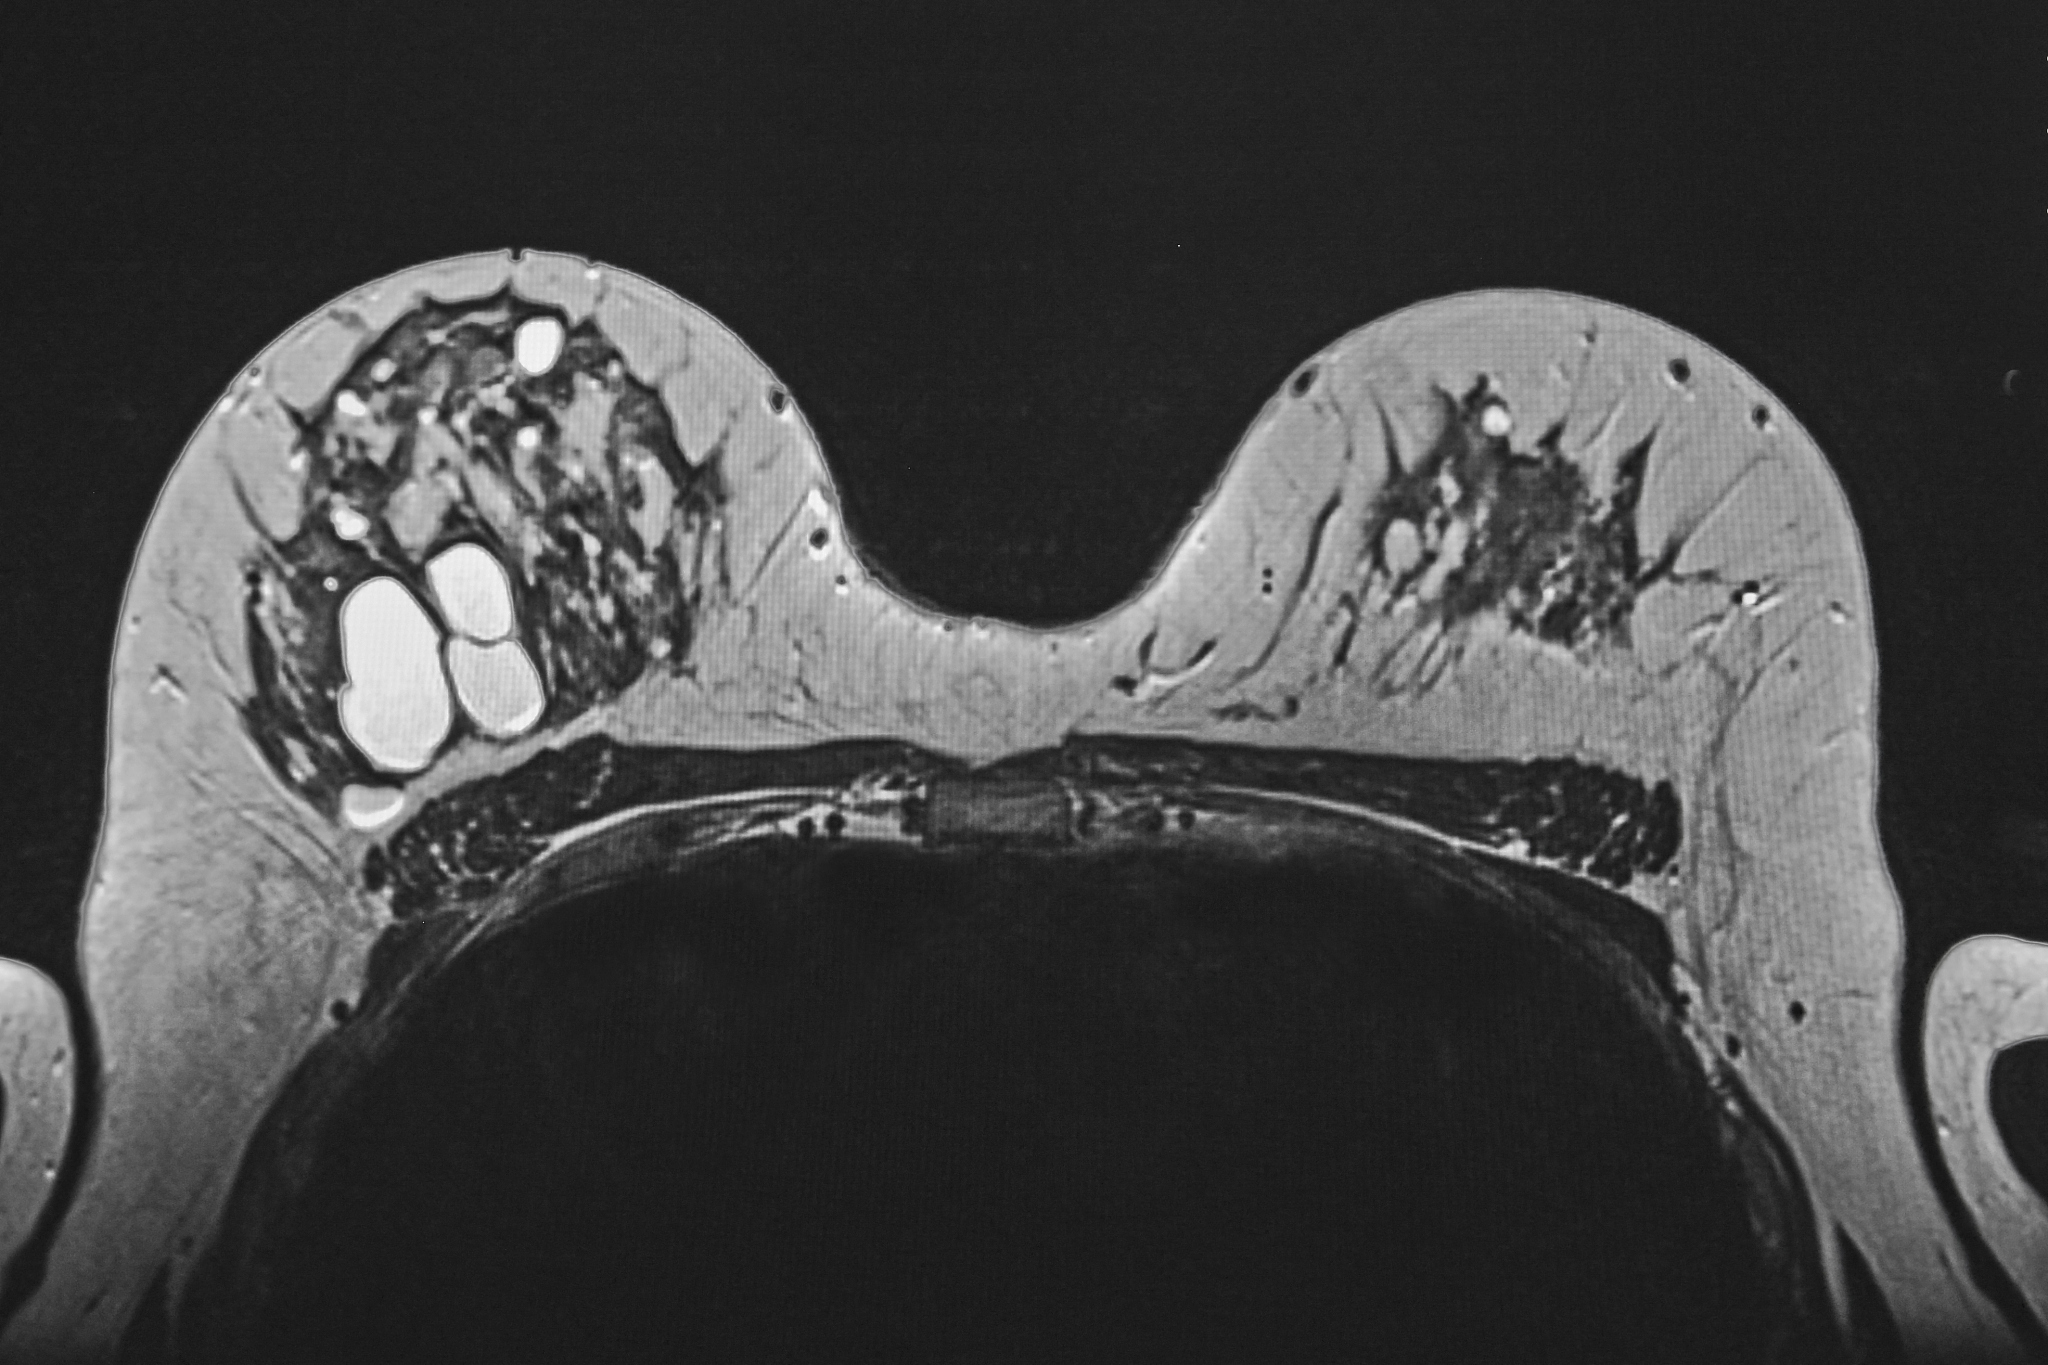

患者女29岁因突发下腹痛2小时入院。急诊CT诊断描述如下:右下腹附件区可见团块状异常密度影范围约6782cm其内部密度不均平扫CT值约9-72HU病灶边界欠清病灶周围可见增粗的血管影盆腔内可见积血积液子宫受压左偏;左侧附件区无殊。请根据以上CT影像描述给出可能的诊断结论。

可能的诊断结论为右侧附件区囊肿性卵巢肿瘤破裂出血。